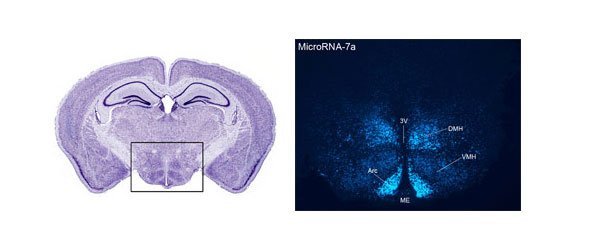

The research aims at investigating and clarifying the neuronal circuitries and hypothalamic mechanisms that control food intake. The expression of protein and transmitter mediators and microRNAs (miRNAs) is investigated in the hypothalamus of normal animals and mouse models of genetic obesity by immunohistochemistry (confocal microscopy), Western blotting, in situ hybridization and RT-PCR. Using laser microdissection microscopy and microarray technology, we try to find novel genes in selected hypothalamic neuronal populations that participate in the regulation of food intake. Since some hypothalamic neuronal populations are under the influence of circulating hormones, such as leptin and ghrelin, special interest is focussed on molecular components of the blood-brain barrier (BBB) in relation to neurons that control energy balance.